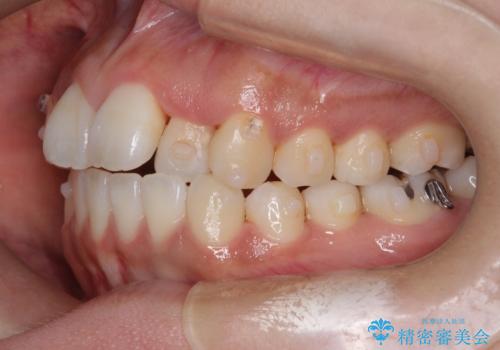

初診時の歯並びの状態としては、上下ともに全体に及ぶの中等度のがたつき(叢生)があり、全特に左上の前歯は1本だけ引っ込んでいる状態でした。

抜歯は行わず上顎の奥のスペースを利用して歯をスライドする方法の他に歯列弓の拡大やディスキング(歯と歯の間の隙間を作る処置)を行い叢生を改善しました。

歯の大きさの不揃いが原因の正中のズレは、ディスキング量を調整することで合わせました。